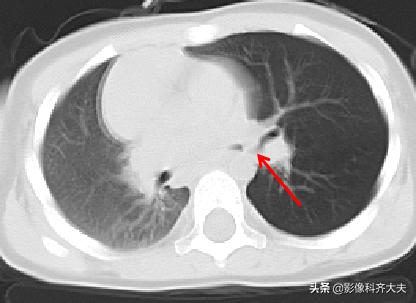

病例5、病史:女,1岁,咳喘12天无好转

轴位图

轴位显示左肺明显肺气肿,左侧支气管似有异常。为进一步明确诊断,遂进行CT三维重建

进行MPR(多平面重组)冠状位重建,清晰显示左侧左侧支气管有异物。

最小密度投影重建对于异物的显示更加清晰,红色箭头所示。